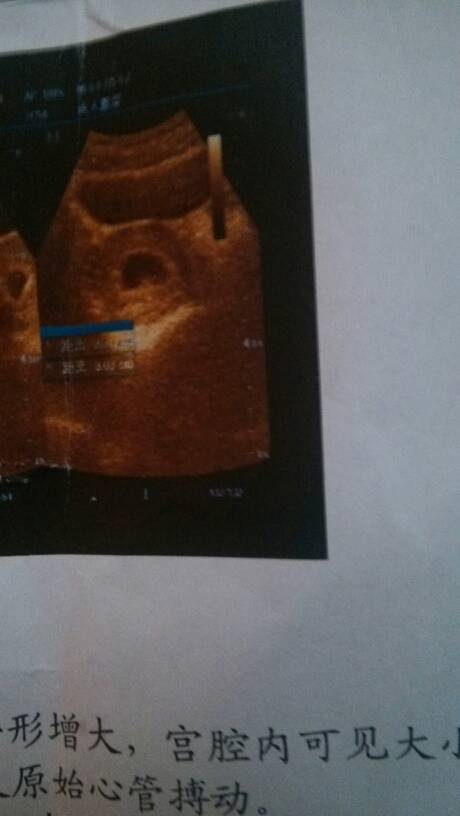

谁能告诉我只是男孩还是女孩呢,好好奇